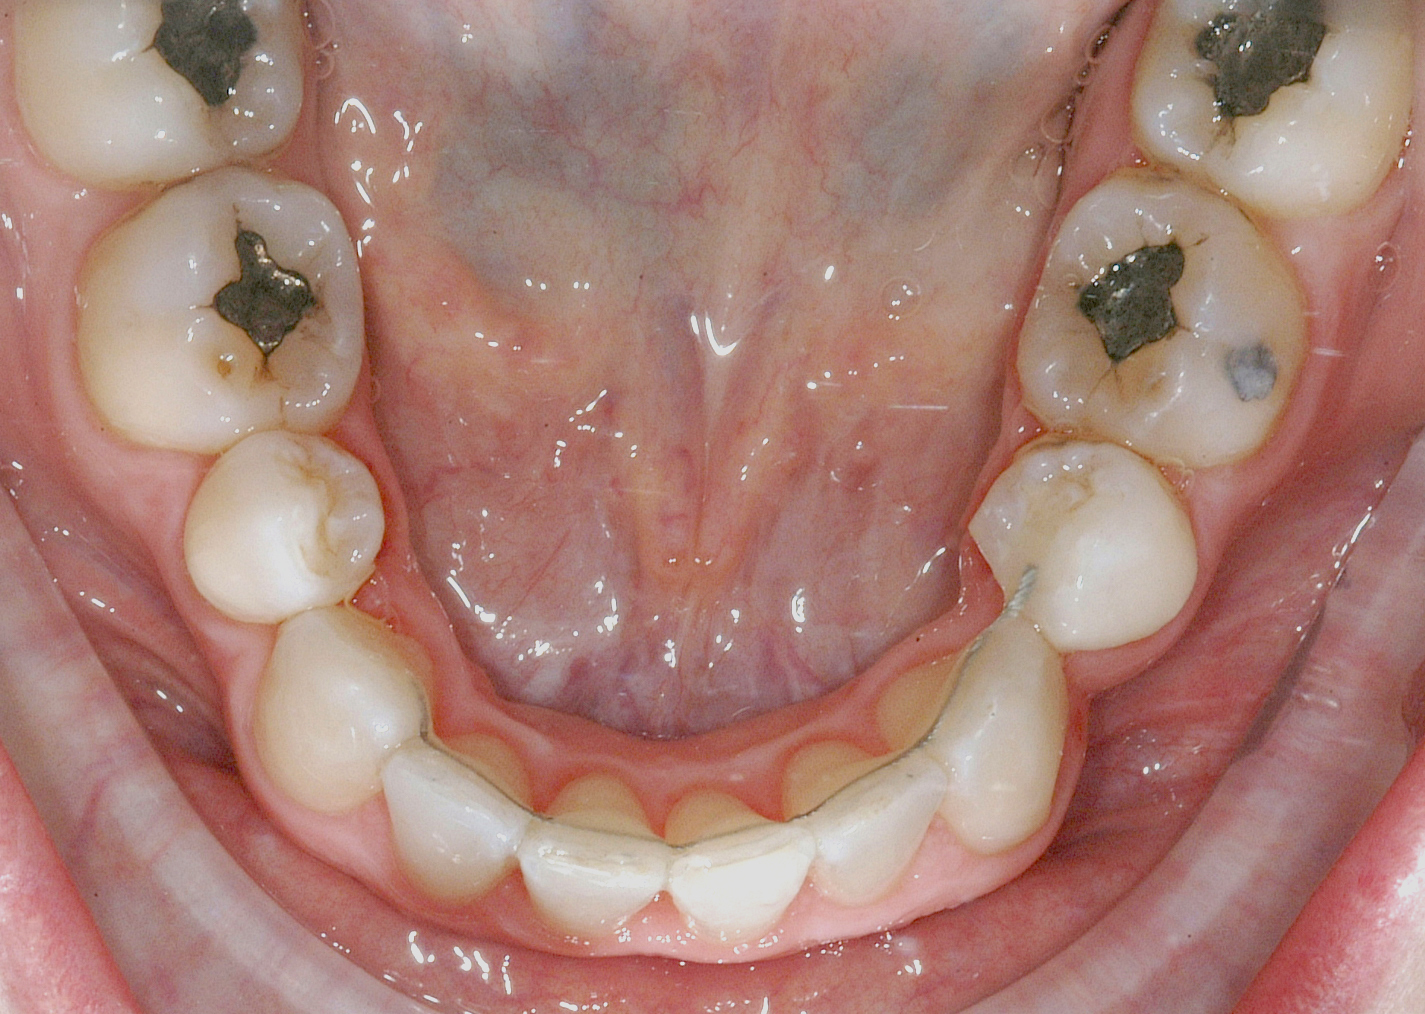

Per la chiusura dello spazio all’arcata inferiore, dopo la preliminare fase di allineamento e livellamento2, con la stessa sequenza iniziale di archi (.014” e poi .016” Nichel-Titanio), è stato temporaneamente applicato un sistema di ancoraggio ausiliario vestibolare, mediante fibre rinforzate, bondate sulla superficie vestibolare di 3.5, 3.6, 3.7 (Figura 4).

Successivamente, per controllare il movimento radicolare distale del canino inferiore sinistro (3.3), è stato applicato un sistema di forze che ha sfruttato: la forza singola distalizzante e di chiusura spazi data dalla catenella elastica con ruolo stabilizzante anche verticale su 3.3, inserita e agganciata in due segmenti, uno mesiale e uno distale, nelle rispettive alette dello slot occlusale del 3.3, e una coppia di forze di uprighting data dall’arco ortodontico .016” Nichel Titanio; quest’ultimo è stato inserito distalmente nello slot ausiliario dell’attacco linguale sul 3.5 ottenuto ripiegando verso occlusale la terza aletta gengivale, e poi nel tubo singolo sul 3.6, e mesialmente, da mesiale verso distale e da gengivale verso occlusale nello slot di 3.3, generando una flessione verticale di secondo ordine, la cui rotazione in senso linguale veniva controllata dalla catenella elastica stessa in appoggio su di esso. Il segmento di arco distale a 3.2 è stato ripiegato in senso gengivo-vestibolare (Figura 5).

Nota tecnica: una volta ottenuto il corretto posizionamento del 3.3, al fine di simmetrizzare l’arcata inferiore e centrare le linee di simmetria, è stata applicata una molla ad anse aperte tra 4.4 e 4.3 su arco .016” in acciaio (Figura 6).